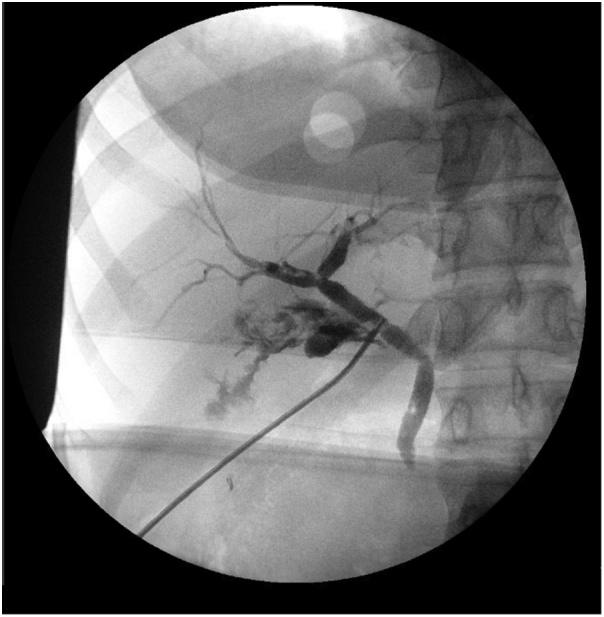

A 34-year-old female presented with signs and symptoms of acute cholecystitis which was confirmed on imaging. She was found to have an accessory cystic duct on laparoscopic cholecystectomy requiring conversion to open laparotomy with intraoperative cholangiogram to delineate the anatomy.

一名34岁女性出现急性胆囊炎的体征和症状,影像学检查得以证实。在腹腔镜胆囊切除术中发现她有一条副胆囊管,需要转为开腹手术并进行术中胆管造影以明确解剖结构。